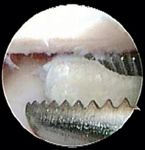

Depending on the severity of the disease, arthroscopic treatment may include fragment removal (Photo 3), débridement of diseased tissues, creation of vascular access by abrasion arthroplasty, forage, microfracture and subtotal coronoid ostectomy. Compared with a traditional surgical arthrotomy, arthroscopy results in better visualization of structures within the joint, less soft tissue trauma, shorter surgery and hospitalization times, decreased risk of infection and shorter recovery times.

Photo 3: Arthroscopic removal of a fragment in a dog with TFMCP.